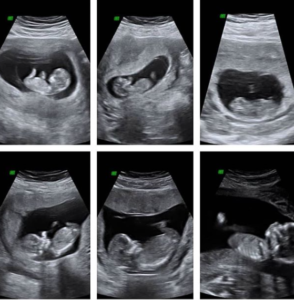

- While at your professional sample appointment, we offer a sneak peek of your baby with our peekaboo heartbeat ultrasound session.

Am I having a boy or a girl? If you do not wish to wait until your 14 week gender reveal ultrasound, you may choose the early gender DNA detection’ blood test as early as 7 weeks of pregnancy.